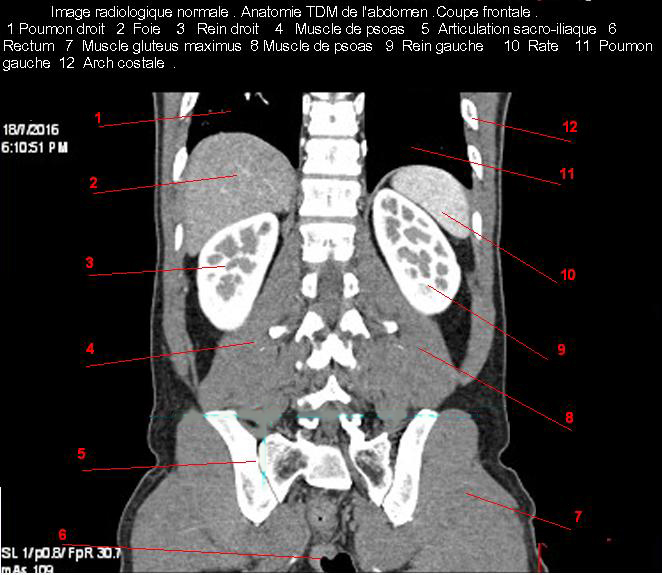

Images radiologique TDM normale de l'abdomen et tube digestif en coupe sagitale ( Coronale )  :

Coupe axiale     Coupe frontale      Coupe  sagitale